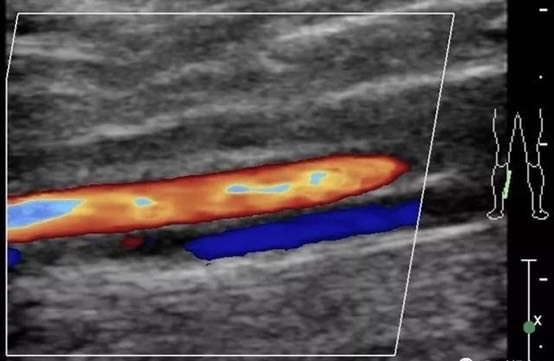

图3 血管彩色多普勒图像

(朝向探头运动血流为红色,背离探头运动血流为蓝色)